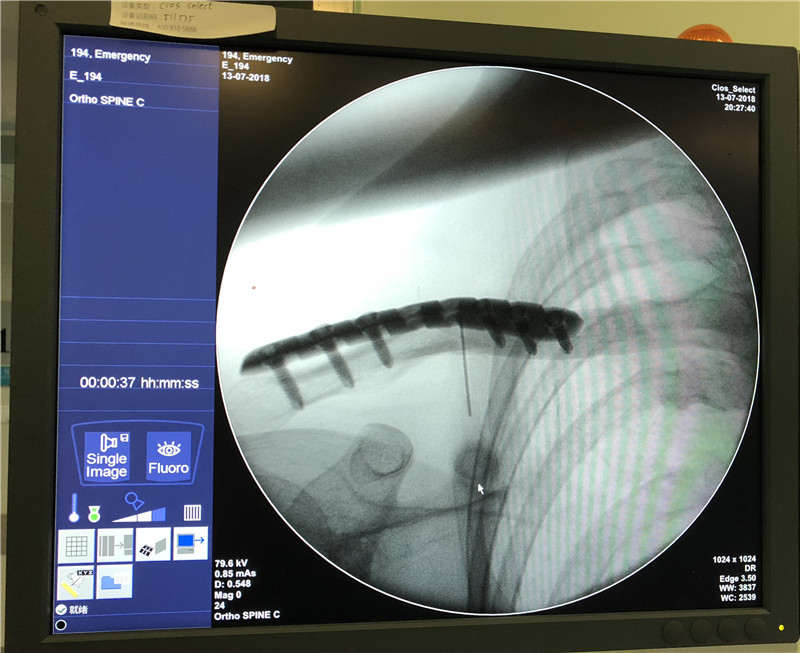

术中定位: